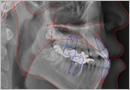

골격성 부정교합의 치료

일반적인 교정치료 즉, 단순한 치아배열이상을 바로잡는 교정치료로서 치료할 수 없는 부정교합으로서 위턱과 아래턱의 크기 부조화가 그 원인입니다. 골격성 교정 문제는 치아의 불규칙 보다는 위아래 턱의 기형이나 위치이상에서 기인하며 다양한 원인으로부터 비롯됩니다

임플란트

인체에 전혀 해가 없는 임플란트 재료가 사람의 턱 뼈와 잘 붙는 현상을 이용하여, 충치나 잇몸병으로 없어진 치아나, 사고 또는 종양 등으로 인하여 뼈와 잇몸이 없는 부분에 대해서 미용 뿐 만 아니라 기능까지 회복시키는 치료를 말합니다. 이런 임플란트를 이용한 치료로 말미암아 기존의 치료 방법으로는 불가능했던 치료가